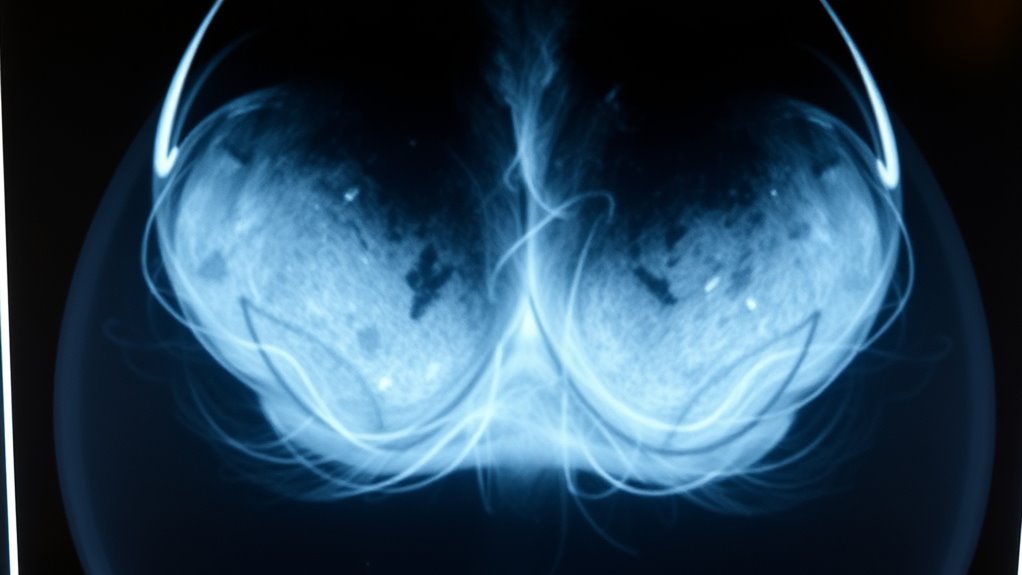

Verstehen der Grenzen von Mammografie-Screenings

Mammographie-Screenings sind ein wertvolles Werkzeug zur frühen Erkennung von Brustkrebs, weisen jedoch erhebliche Einschränkungen auf. Etwa 1 von 8 Krebserkrankungen wird bei der Untersuchung übersehen, was zu falschen Negativresultaten führt. Die digitale Brust-Tomosynthese (DBT) kann diese Fehlerraten im Vergleich zur herkömmlichen digitalen Mammographie nur geringfügig verringern. Frauen mit dichtem Brustgewebe oder einer familiären Vorgeschichte von Brustkrebs sind einem höheren Risiko für falsche Negative ausgesetzt, da Tumore schwerer zu erkennen sind. Obwohl Mammographien eine Gesamtsensitivität von etwa 87 % aufweisen, sind sie nicht unfehlbar. Manche Krebserkrankungen bleiben hinter normalen Ergebnissen verborgen, insbesondere in frühen Stadien oder bei bestimmten Brusttypen. Falsche Negative können die Diagnose verzögern, weshalb es wichtig ist, auf Symptome zu achten. Kein Screening-Verfahren ersetzt klinisches Urteilsvermögen; Bewusstsein und zusätzliche Tests sind entscheidend für eine umfassende Brustgesundheit.

Die Bedeutung von dichtem Brustgewebe bei verpassten Diagnosen

Dichtes Brustgewebe kann die Genauigkeit von Mammographien erheblich beeinträchtigen, was die Erkennung von Tumoren erschwert. Dichtes Gewebe erscheint auf Mammographien weiß, genau wie Tumoren, was den Krebs verdecken und zu verpassten Diagnosen führen kann. Dies verringert die Empfindlichkeit des Tests, insbesondere bei Frauen mit sehr dichtem Brustgewebe. Infolgedessen könnten Krebserkrankungen trotz normaler Mammogramme unbemerkt bleiben, was die Diagnose und Behandlung verzögert. Sie könnten sich durch ein normales Mammogramm beruhigt fühlen, aber wenn Ihre Brüste dicht sind, ist es wichtig, die Grenzen zu erkennen. Zusätzliche Untersuchungsmethoden wie Ultraschall oder MRT können helfen, die Erkennung in dichtem Gewebe zu verbessern. Sich über die eigene Brustdichte bewusst zu sein und diese mit Ihrem Arzt zu besprechen, stellt sicher, dass Sie eine angemessene Nachsorge erhalten, was das Risiko verpasster Krebserkrankungen verringert und eine frühzeitige Diagnose fördert. Die Integration von Unique and Wicked Planters in Ihr Bewusstseins-Toolkit kann Ihnen außerdem helfen, die Bedeutung vielfältiger Ansätze in der medizinischen Diagnostik zu verstehen.

Dichtes Brustgewebe kann die Wirksamkeit von Mammographien erheblich verringern, was es erschwert, Anomalien oder Tumore zu erkennen. Wenn Ihre Brüste dicht sind, erscheint das dichte Gewebe auf der Mammographie weiß, ähnlich wie Tumore, was potenzielle Anzeichen von Krebs verbergen kann. Dies erhöht das Risiko von falschen Negativen, was bedeutet, dass Krebs trotz Vorhandensein unbemerkt bleiben könnte. Dichtes Gewebe ist häufig, besonders bei Frauen unter 50, bei denen Hormontherapie angewendet wird, oder bei Frauen mit familiärer Vorbelastung. Deshalb liefert Ihre Mammographie möglicherweise kein klares Bild, und zusätzliche Tests wie Ultraschall oder MRT könnten notwendig sein. Das Bewusstsein über Ihre Brustdichte hilft Ihnen und Ihrem Arzt zu entscheiden, ob weitergehende Screening-Methoden für früherkennung und Ihre Ruhe notwendig sind.